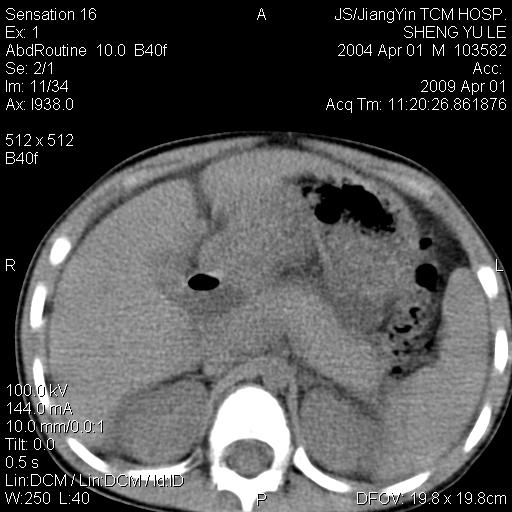

m,5岁。尿痛尿频数天。既往无病史。ct平扫腹盆腔积液。膀胱壁明显增厚。另可见心包增厚。wbc5万,骨髓穿等结果。请指教。

膀胱影像表现结合临床应该是急性膀胱炎症,但为什么有腹水呢?双肾输尿管无扩张,泌尿系压力应该不大不至于引起尿外渗,应该是腹膜感染引起的,但楼主没有提及相关症状,腹膜及膀胱结核?患者白细胞5万(结核不至于这么高啊),脾脏增大,是不是有白血病?进一步检查。。